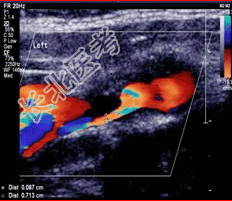

- 简答题2、颅脑CT:未发现明显异常。颈动脉超声检查如下图。根据图像判断病变程度是什么?